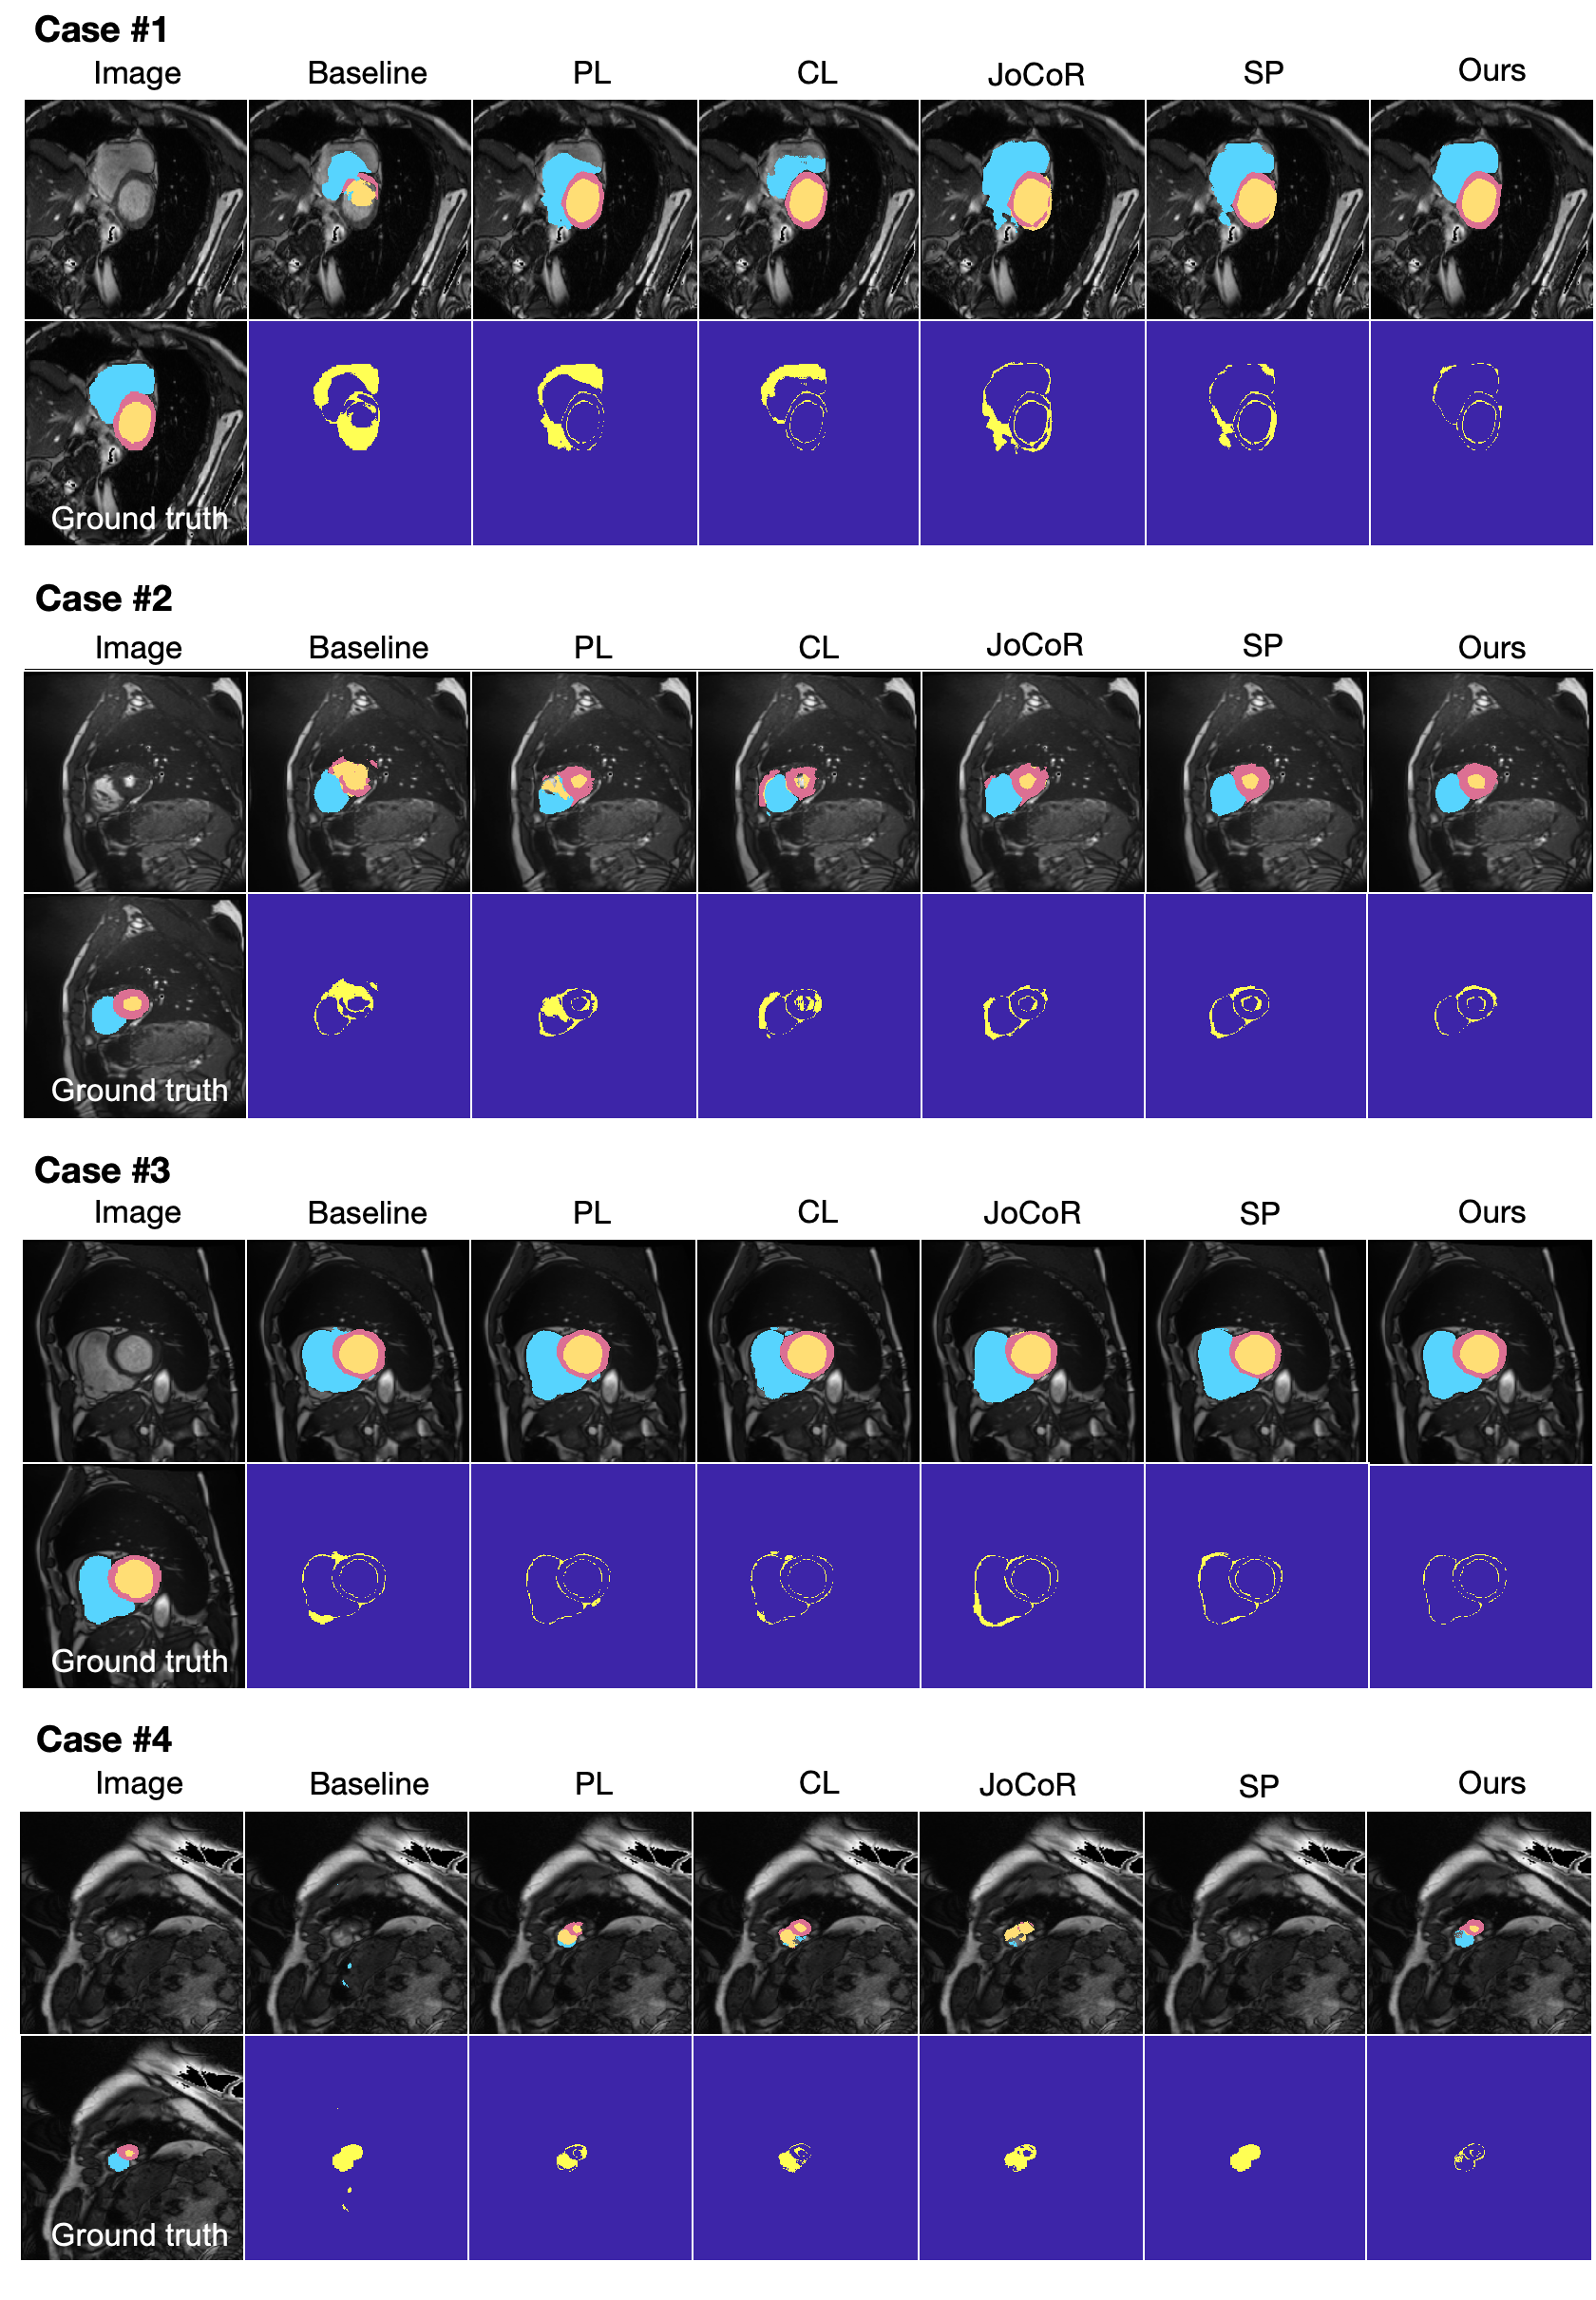

Refer to caption

Figure 6: Qualitative results of different methods on the ACDC dataset (B-model, α2=70%subscript𝛼2percent70\alpha_{2}=70\%italic_α start_POSTSUBSCRIPT 2 end_POSTSUBSCRIPT = 70 %, β2=10subscript𝛽210\beta_{2}=10italic_β start_POSTSUBSCRIPT 2 end_POSTSUBSCRIPT = 10), where right ventricle (RV) regions are highlighted in blue, myocardium (Myo) regions in red, left ventricle (LV) regions in orange, and discrepancies between network-produced results and ground truths are highlighted in yellow.

3.5 Generalization Validation

To assess the generalization ability of the proposed method across different datasets and segmentation tasks, we conduct additional validation experiments on the ACDC dataset. Specifically, we focus on segmenting three different organs—left ventricle (LV), right ventricle (RV), and myocardium (Myo)—from MRI images. Fig. 6 provides visual examples of segmentation results produced by different methods (produced by B-model with α2=70%subscript𝛼2percent70\alpha_{2}=70\%italic_α start_POSTSUBSCRIPT 2 end_POSTSUBSCRIPT = 70 %, β2=10subscript𝛽210\beta_{2}=10italic_β start_POSTSUBSCRIPT 2 end_POSTSUBSCRIPT = 10). It is shown that our method produces results that are most similar to the ground truths. Table 3 presents the quantitative results, including the analysis of both the B-model and L-model for each method. The results demonstrate that the proposed method outperforms competing methods across the three-organ segmentation tasks. Besides, the improvement of the stability and sustained noise-resistance ability of the network is particularly evident compared with other four methods. These findings on the ACDC dataset demonstrate the generalization capability of our method, implying its noise-resistance ability across different datasets and segmentation tasks.